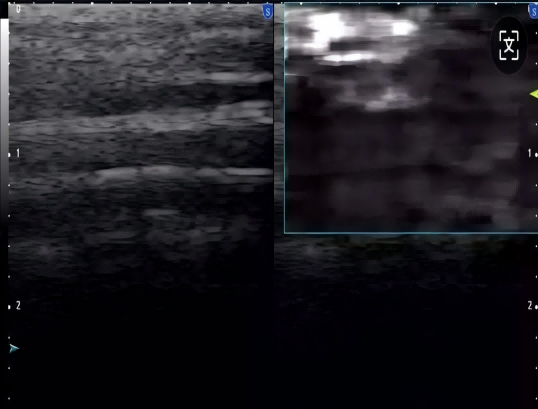

Freehand elasticity imaging: 徒手弹性成像(FEI)

• 徒手弹性成像是通过移动探头对检测部位进行挤压使组织产生运动,并利用回波信号进行运动检测得到表征组织弹性的应变图像

• 基于应力的弹性应变成像,提供组织软、硬病变的诊断信息

• 业界最高帧率 50fps vs 20fps

• 业界最大检测区域—全器官检测